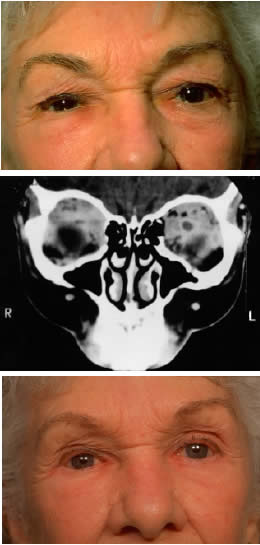

Meningiomas of the sphenoid wing are prone to extend into the orbit along the lateral wall as an en plaque component (Fig. 4). These desmoplastic, infiltrative lesions generally have some element of hyperostosis. The orbital and visual manifestations reflect the location of the mass, with the more medial tumors causing cranial nerve palsies, visual deficits, and venous obstructive signs and symptoms (e.g., edema, chemosis). More remote tumors are manifested by raised intracranial pressure or mass effect. Tumors of the greater wing of the sphenoid are evidenced by fullness of the temporalis fossa and proptosis, with intracranial symptoms occurring as a late symptom (Fig. 5). Olfactory groove meningiomas present with lost sense of smell, personality changes, papilledema, or apical orbital infiltration or compression.

Fig. 4. A 36-year-old white woman presented with a 3-month history of progressive left proptosis associated with a retrobulbar pressure sensation. On external examination, she had bossing of the temporalis fossa and a proptosis of 9 mm axially, with a slight downward displacement of the globe. Ocular ductions were full, and there was no evidence of optic nerve compromise. CT scan on axial (A) and coronal (B) views confirmed a hyperostosing sphenoid wing meningioma with soft tissue components in the posterolateral orbit and anterior middle cranial fossa. During the next 20 months, her proptosis progressed to 11 mm, accompanied by increasing headaches and ocular pain, ocular restriction, and blurred vision in abduction. She underwent tumor resection with a combined frontotemporal orbitozygomatic approach, and she remains without evidence of recurrence 5 years after surgery. Visual function was preserved, and proptosis decreased to 2 mm.

Fig. 5. A 48-year-old Chinese woman had undergone previous frontotemporal craniotomy and partial excision of a left sphenoid wing meningioma. She presented 6 years later with progressive proptosis, visual loss, and numbness of the left cheek and upper teeth that developed during the preceding 2 years. On external examination, she had fullness of the temporalis fossa, an axial proptosis of 11 mm, and downward displacement of the left globe 2 mm (A). Ocular ductions were moderately restricted in all fields of gaze. She had no light perception, marked optic disc pallor, and an optociliary shunt vessel. CT scan revealed an extensive regrowth of meningioma involving the sphenoid wing, with soft tissue components in the temporalis and middle cranial fossae, parasellar region, and orbit, shown here on axial view (B). The lesion also involved the cavernous sinus and pterygopalatine fossa. She underwent a combined resection via the frontotemporal orbitozygomatic approach, followed by radiotherapy (50 Gy in 25 fractions over 5 weeks) for residual components in the cavernous and sphenoid sinuses. Two years after surgery, she remains comfortable and without radiographic evidence of tumor regrowth. Proptosis was reduced to 1 mm axially.